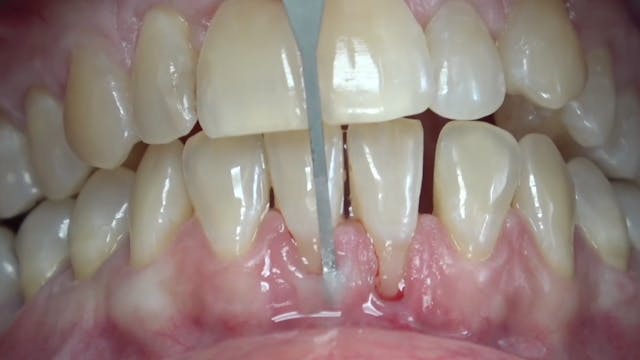

CLINICAL VIDEO Implant Gingival Recession Treated with a Tunneling Procedure and

Gingival recession, a common periodontal condition characterized by the exposure of tooth roots due to gum tissue loss, poses aesthetic concerns and increases susceptibility to root c...